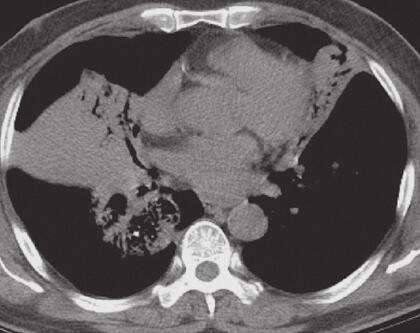

入院后给予左氧氟沙星注射液抗感染,盐酸氨溴索祛痰、多索茶碱解痉治疗,咳嗽、咳痰及呼吸困难症状改善不明显。2014年11月29日胸部CT示(图1):双肺可见大片状及片絮状高密度阴影,内可见通气征。2014年12月2日支气管镜检查提示:右肺主支气管及右肺中间段支气管充血明显,黏膜欠光滑,可见管腔轻度狭窄。活检病理提示:黏膜慢性炎症。患者感气喘,查体肺部可闻及散在哮鸣音。给予甲泼尼龙注射液40mg,1次/日,静点,3天后患者自觉气喘等症缓解,但仍有咳嗽及呼吸困难,夜间咳嗽明显2014年12月10日再次行支气管镜检查,给予TBLB,仍提示黏膜慢性炎症。请感染科会诊拟给予抗结核治疗。患者不耐受,拒绝行抗结核治疗。再次行支气管镜检查,TBLB,病理结果提示:左肺上叶舌段活检:结合HE形态及免疫表型符合B细胞非霍奇金淋巴瘤。右下活检:黏膜慢性炎,间质炭末沉积。

图1 2014年11月29日肺部CT

双肺实变病灶并伴有空气支气管征

2. 主要表现为反复咳嗽、咳痰、呼吸困难,查体双肺散在干啰音及湿啰音,胸部CT检查提示双肺大片状及片絮状阴影,可见支气管征,纵隔淋巴结肿大。反复行TBLB才明确诊断。

肺原发性淋巴瘤影像学表现多种多样。宋伟等将其归纳为:①结节肿块型:最常见,多为单发病灶,边界模糊,病灶内可见支气管充气征,部分病灶内可见空洞和液平;②肺炎或肺泡型:表现为沿肺段或肺叶分布的模糊斑片影,可见支气管充气征,偶见空洞;③间质型:最少见,表现为弥散的细或粗糙网状结构或网状小结节或毛玻璃样变;④粟粒型:表现为直径小于1cm的多发小结节,边界粗糙,无支气管充气征。本例属于肺炎型,见支气管充气征,未见明显肿块影,因而给诊断造成困难,一开始被误诊为肺炎,最终反复行TBLB才得以明确诊断。

下述表现有助于PPL诊断的可能:①年龄在60岁左右,无症状或咳嗽、咳少量痰,有胸闷、胸痛、呼吸困难等症状者;②肺部影像表现为结节、肿块或实变病灶并伴有空气支气管征,合并肺间质性改变,无肺门及纵隔淋巴结的肿大,无胸膜增厚及胸腔积液;③病灶变化趋势不大,并且长期存在。病理学是确诊的关键,而病理标本获取途径主要通过TBLB、PTNB、内科胸腔镜、VATS及开胸手术切除。对此我们的经验是,首先选用损伤性小、患者的依从性较好的方式,如TBLB、PTNB、内科胸腔镜下胸膜活检,并可多次活检以提高阳性率。但是若上述诊断方法仍不能明确诊断或诊断所需时间较长时仍应,再考虑采取VATS等外科介入方式进行活检、及时诊断。